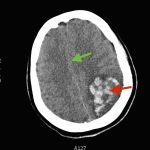

The patient’s head CT showed a significant area of hyperdensity consistent with an intracranial hemorrhage located within the left frontal parietal lobe (red arrow). Additionally, there is rightward midline shift up to 1.1cm (green arrow) and entrapment of the right lateral ventricle (blue arrow).